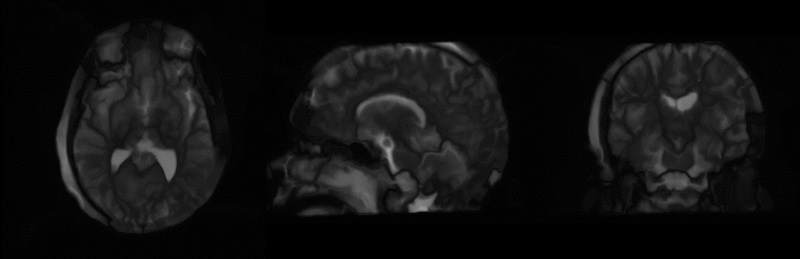

Experiment 2: Co-registration of Subject Specific Multi-modal MRI and DTI

Data before registration.

After affine registration.

After BSpline registration.

After unconstrained diffeomorphic demons.